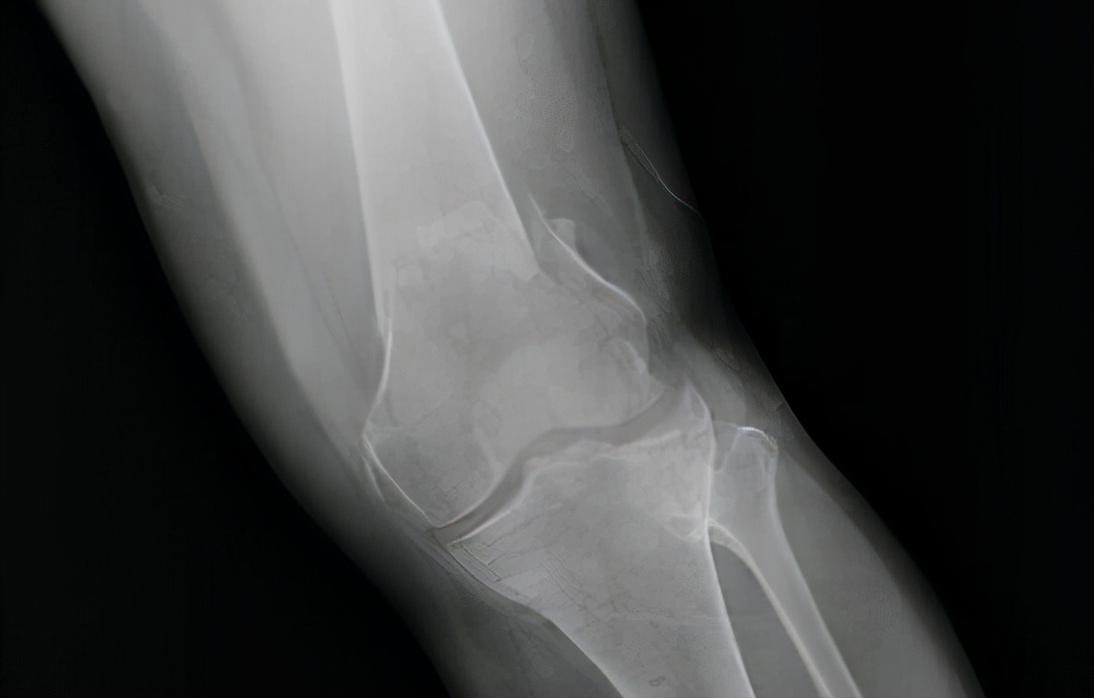

而来医院求医问药的老大爷、老大妈们有什么问题呢?做了CT后我们发现,他们的髌骨关节的软骨在积年累月的股骨撞击下,只剩下薄薄的一层了,股骨远端已经和髌骨“撞”在了一起,因此当他们上楼梯时,才会有清脆的骨摩擦的声音。

而且,我们还能在他们的影像上,发现它们股骨的远端有一些淡白色的凸起。没错,那就是骨质增生,也被称为骨赘。

不过这种属于生理增生,不属于疾病的范畴,出现骨赘的原因是长期的骨与骨之间的碰撞摩擦,导致这个地方的成骨细胞和破骨细胞异常活跃,最终长出来一小块“骨赘”,然后这块骨赘在患者活动的时候卡压神经、软组织、血管,这能不疼吗?

如果进入了中期,那么此时患者的典型症状为久站、步行后均会出现髌骨区域的疼痛,且在影像图片上看到有骨赘的形成,那么此时应该选用打封闭针止痛,或者补充玻璃酸钠等方式及时处理,止痛后再想办法恢复膝关节的功能。